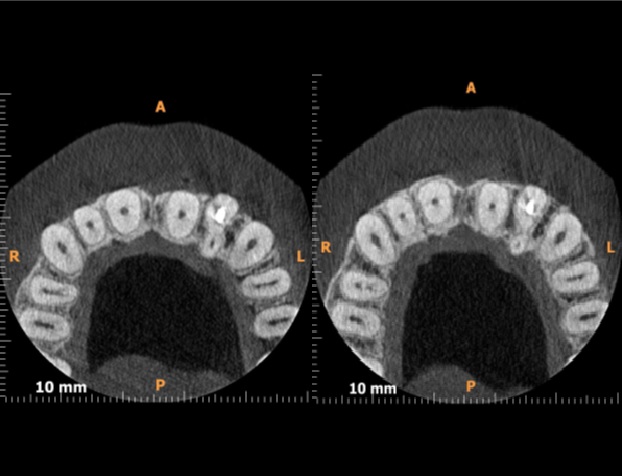

- Wykonano dodatkowe badanie tomografii stożkowej CBCT, w którym stwierdzono występowanie w zębie 22 dwóch odrębnych korzeni oraz dwóch kanałów. Kanał policzkowy był wypełniony na pełną długość roboczą, natomiast kanał podniebienny nie został opracowany.

Streszczenie: Każda grupa zębów ma swoje specyficzne cechy morfologiczne, które pozwalają na ich szybką identyfikację. Ząb sieczny boczny górny zwykle ma jeden prosty korzeń i jeden kanał, który może ulegać zakrzywieniu, najczęściej w kierunku dystalnym. Zdarza się jednak, że zęby te mają dwa, a nawet trzy kanały. Badania dwuwymiarowe nie dają pełnego obrazu trójwymiarowej anatomii systemu korzeniowego. Tomografia stożkowa CBCT umożliwia dokładne poznanie morfologii systemu korzeniowego oraz kanałowego i pozwala na skuteczne zaplanowanie leczenia. Celem pracy jest przedstawienie przypadku 32-letniej pacjentki, u której na zdjęciu pantomograficznym zauważono leczony endodontycznie ząb 22, którego kanał nie został wypełniony w całości. Wykonano dodatkowe badanie tomografii stożkowej CBCT, w którym stwierdzono występowanie w zębie 22 dwóch odrębnych korzeni oraz dwóch kanałów. Kanał policzkowy był wypełniony na pełną długość roboczą, natomiast kanał podniebienny nie został opracowany.